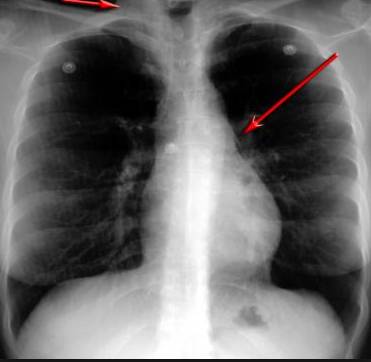

并且,因?yàn)楹粑到y(tǒng)結(jié)構(gòu)復(fù)雜,在體檢時(shí)醫(yī)生很難通過(guò)一種檢測(cè)手段,判定早期患者的病情。

使用這臺(tái)掃描儀,將直接把器官變成3D圖形!細(xì)微的毛細(xì)血管,幾毫米大的肺泡和支氣管,都將能看的一清二楚!

你的每一個(gè)氣泡,每一段支氣管,哪兒有病變都清清楚楚的將展示在醫(yī)生面前!

也就是說(shuō)在一切都還沒(méi)開(kāi)始惡化前,把這些有問(wèn)題的器官組織都暴露的一清二楚:

不同于CT掃描,需要從同一角度,拍下無(wú)數(shù)張器官二維圖,從而搭建3D器官結(jié)構(gòu)圖那般費(fèi)時(shí)費(fèi)力。

4D掃描儀將直接從不同角度,同時(shí)對(duì)人體器官進(jìn)行掃描,然后通過(guò)計(jì)算機(jī)算法進(jìn)行快速成像。CT需要花幾小時(shí)才能完成的工作,

4D掃描將在幾秒內(nèi)完成!

當(dāng)大家還在為B超、X光、CT哪個(gè)輻射更少而爭(zhēng)論不休時(shí),這臺(tái)新機(jī)器已經(jīng)比現(xiàn)有掃描儀少20%的輻射

沒(méi)有這項(xiàng)新技術(shù),醫(yī)生在做體檢的時(shí)候,很難通過(guò)一種測(cè)試斷定一個(gè)人是否有呼吸系統(tǒng)疾病。

可是現(xiàn)在他們不但能看到整個(gè)肺部的3維結(jié)構(gòu)圖。還能看到空氣進(jìn)入人體后的所有微小變動(dòng)!